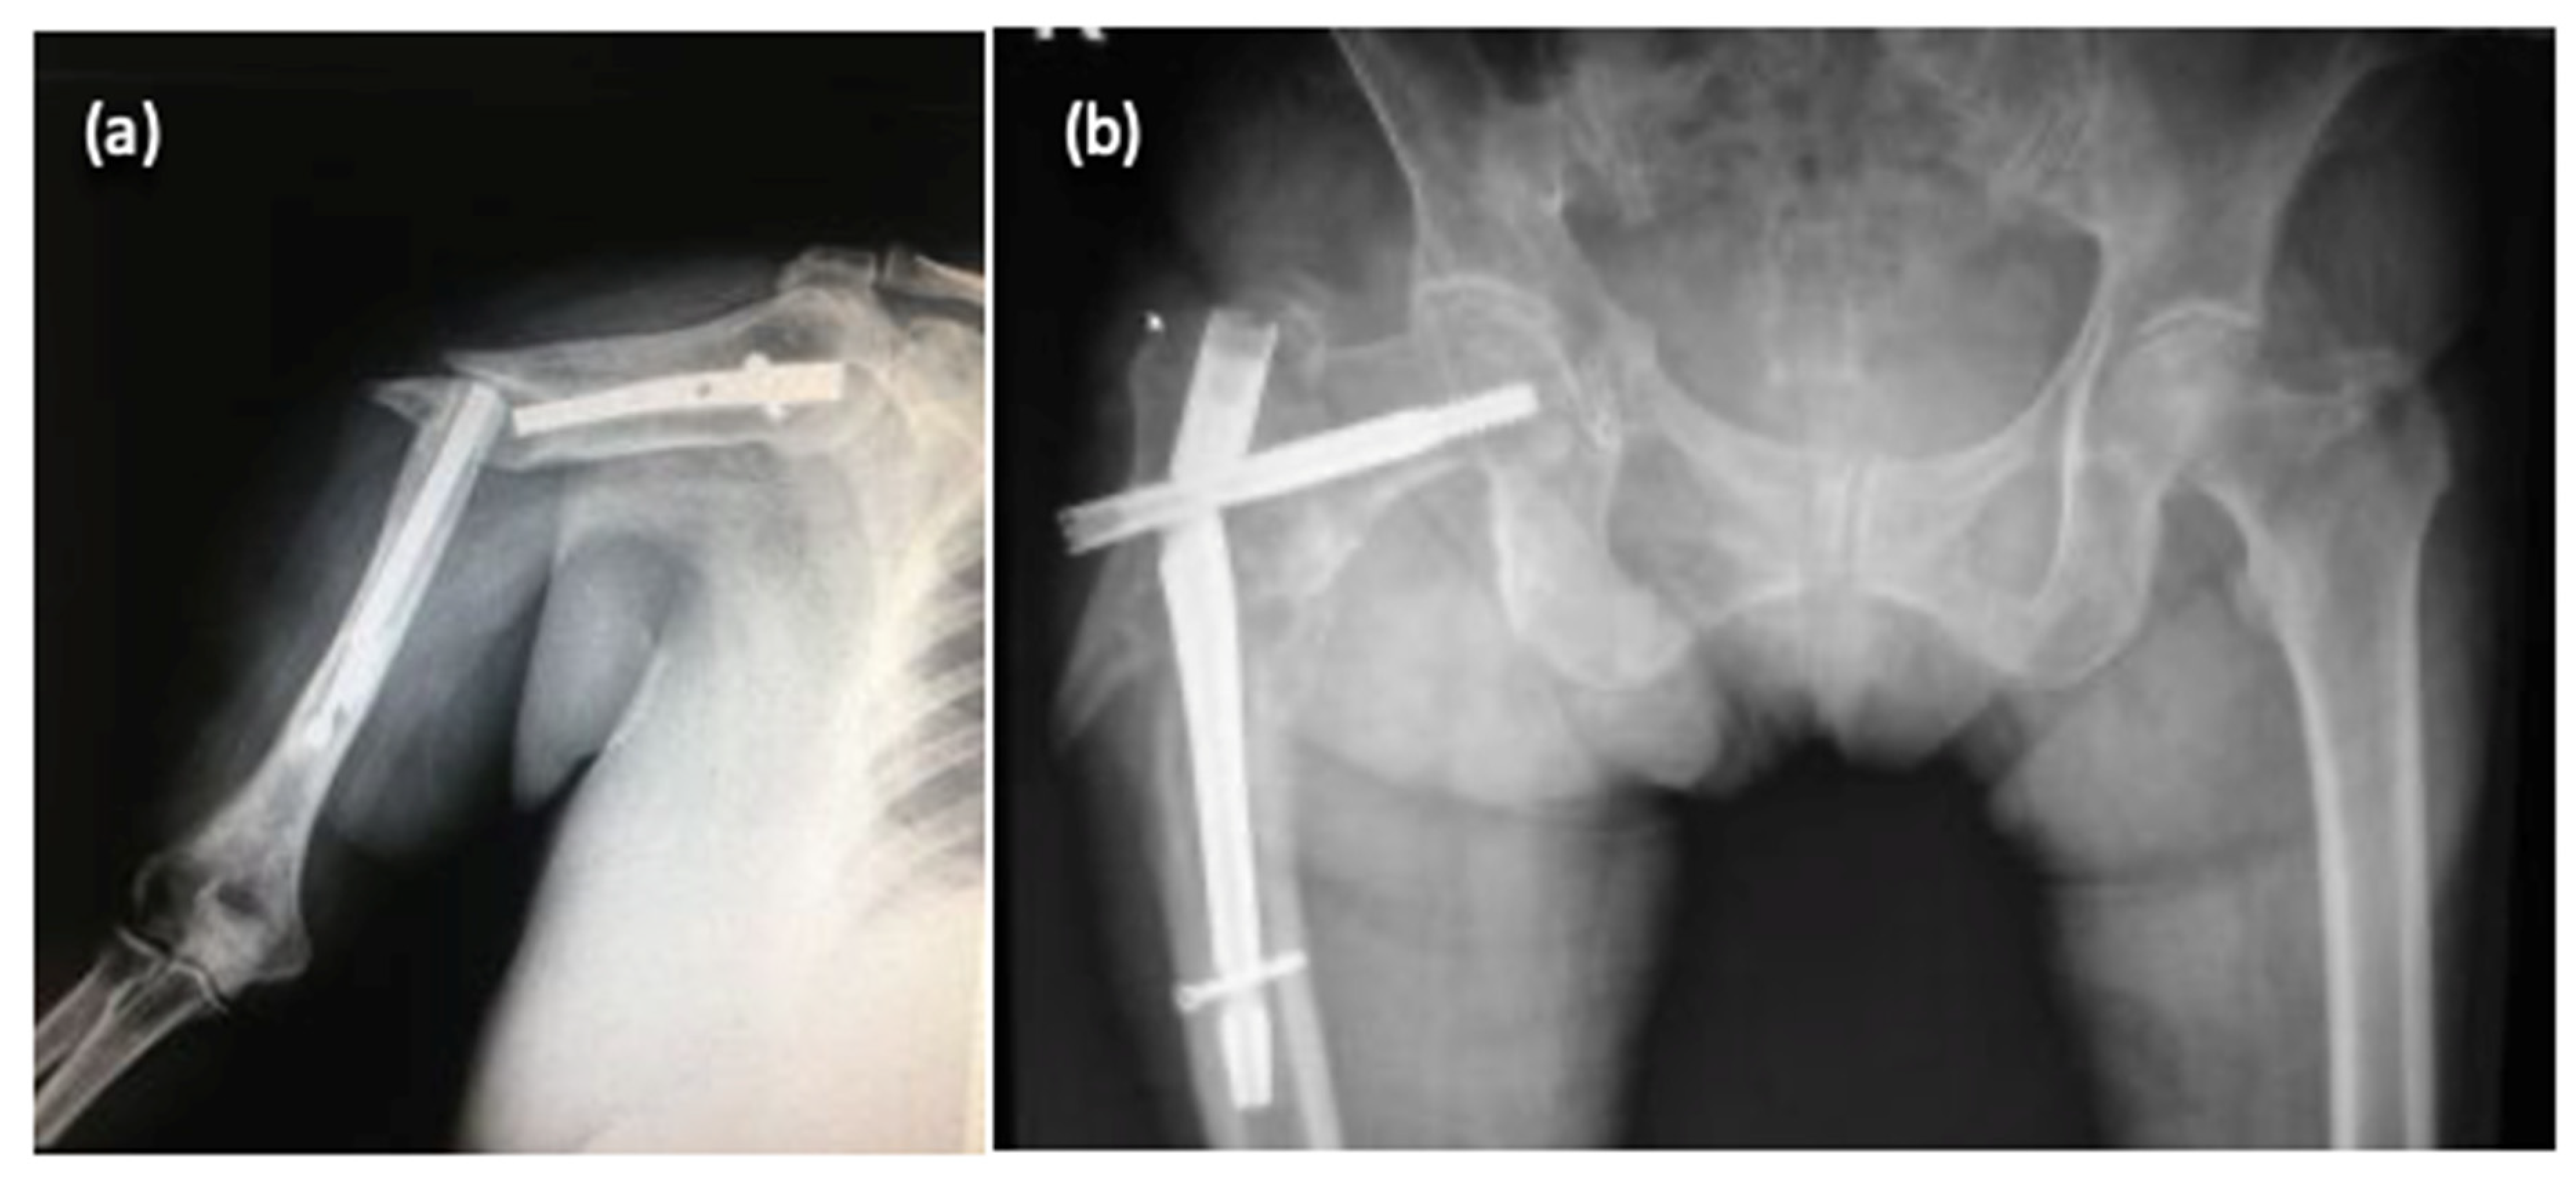

Diagnosis of implant failure was confirmed either by standard radiological examination during regular follow-up visits, or on admission for patients with inciting events and new symptoms generated by implant deterioration. Some radiographic images showing the aspect of deteriorated osteosynthesis implants are presented in Figure 2.

Figure 2.

Radiological aspects of fractures with deterioration of osteosynthesis material: humerus fracture (a) and femoral fracture (b).

Images were assessed focusing on quality of reduction, implant type adequacy, size, and position. Retrieval of broken implants was performed with special care not to cause more damage, especially to the fracture surface.